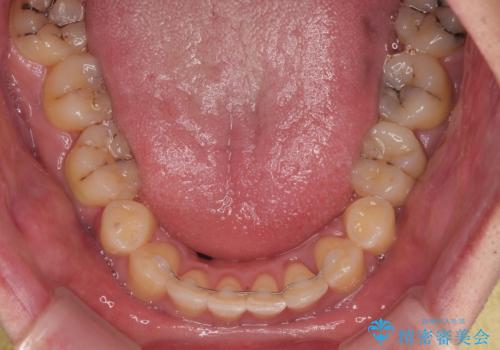

上顎歯列幅を側方に拡大するとともに、歯列全体を後方に移動させるためのアンカースクリューと補助装置を使用し、上顎左右第一小臼歯2本、下顎左右第二小臼歯2本、計4本を抜歯し、ワイヤー装置にて矯正治療を行うこととしました。

上下前歯の前後差が非常に大きく、3年以上の治療期間が予想されましたが、無事に3年間ちょうどで仕上げることができました。